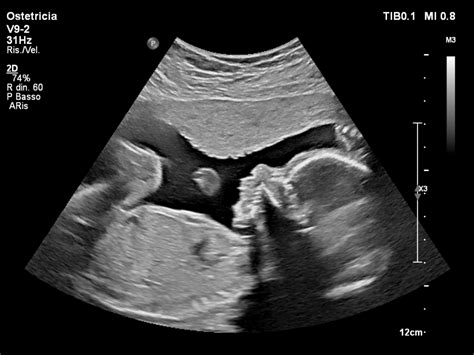

Un punto particolarmente rilevante nel percorso di Milani Comparetti fu la scoperta della motricità fetale, resa possibile dall’incontro con gli ostetrici Ianniruberto e Tajani di Terlizzi nella seconda metà degli anni ’70. Questo incontro ebbe almeno tre effetti fondamentali:

Ciò ha portato all'interpretazione funzionale della motricità fetale (Milani Comparetti, 1981), ipotesi che oggi trova sempre più sostenitori. Ha rinforzato il riconoscimento della partecipazione attiva del feto nel determinismo del travaglio e del parto e, di conseguenza, le raccomandazioni per la valutazione prenatale della salute fetale e la prevenzione del danno ipossico-ischemico perinatale.

Consapevolezza della Precoce Produzione Endogena di Pattern Motori: Si è compreso che lo sviluppo motorio non avviene per graduale maturazione di movimenti dapprima grossolani o poco specifici, bensì attraverso la precoce produzione endogena di pattern motori geneticamente determinati (meccanismi di autopoiesi e feed-forward). Questi pattern, definiti "pattern motori primari", sono già tutti disponibili a 20 settimane di età gestazionale. La loro successiva utilizzazione funzionale avviene secondo un meccanismo modulare epigenetico, culminando nelle "funzioni delle funzioni motorie" e, infine, nella funzione comportamentale che si manifesta nell'interazione relazionale e sociale. Su questo si fonda la nuova proposta semeiotica del 1982. Come ricordava Milani (1985), "la modularità e l’epigenesi sono riconoscibili ben oltre il solo sistema della motricità e riguardano anche i sistemi percettivo, emotivo, cognitivo e anche interattivo. È anzi legittimo allargare il campo della modularità epigenetica anche a categorie dell’essere come la coscienza, l’inconscio, il rapporto io-mondo e io-tempo, il doppio statuto soggetto-oggetto del corpo e tante altre. Tutto questo repertorio innato è evocabile dall’esperire epigenetico secondo il modello interattivo".